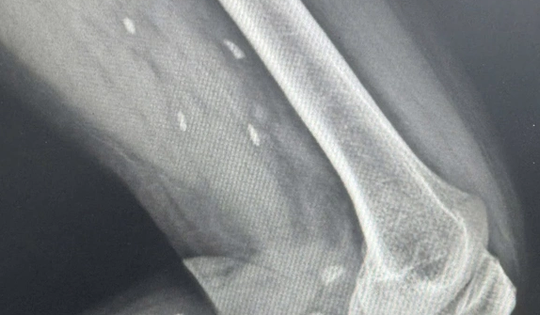

Thói quen nhiều người Việt mê mẩn khiến sán “làm tổ” dưới da mà không hay biết

22/01/2026 10:19

Một người đàn ông có trệu chứng mệt mỏi, đau nhức nhiều ở vùng chân, lưng, hạn chế vận động… nên đến viện khám. Bác sĩ phát hiện các mô vùng xương đùi và cẳng chân bệnh nhân có nhiều kén sán kích thước như hạt gạo.